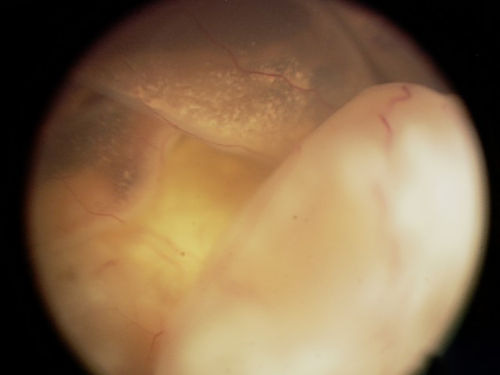

This is an EUA picture of retinoblastoma tumor group C. Tumor group C has moderate risk of losing the eye. Group C tumors are mostly well-defined with small amounts of spread or seeding.

Tumor Group C

The tumor is mostly well-defined but has small amounts of spread or seeding.